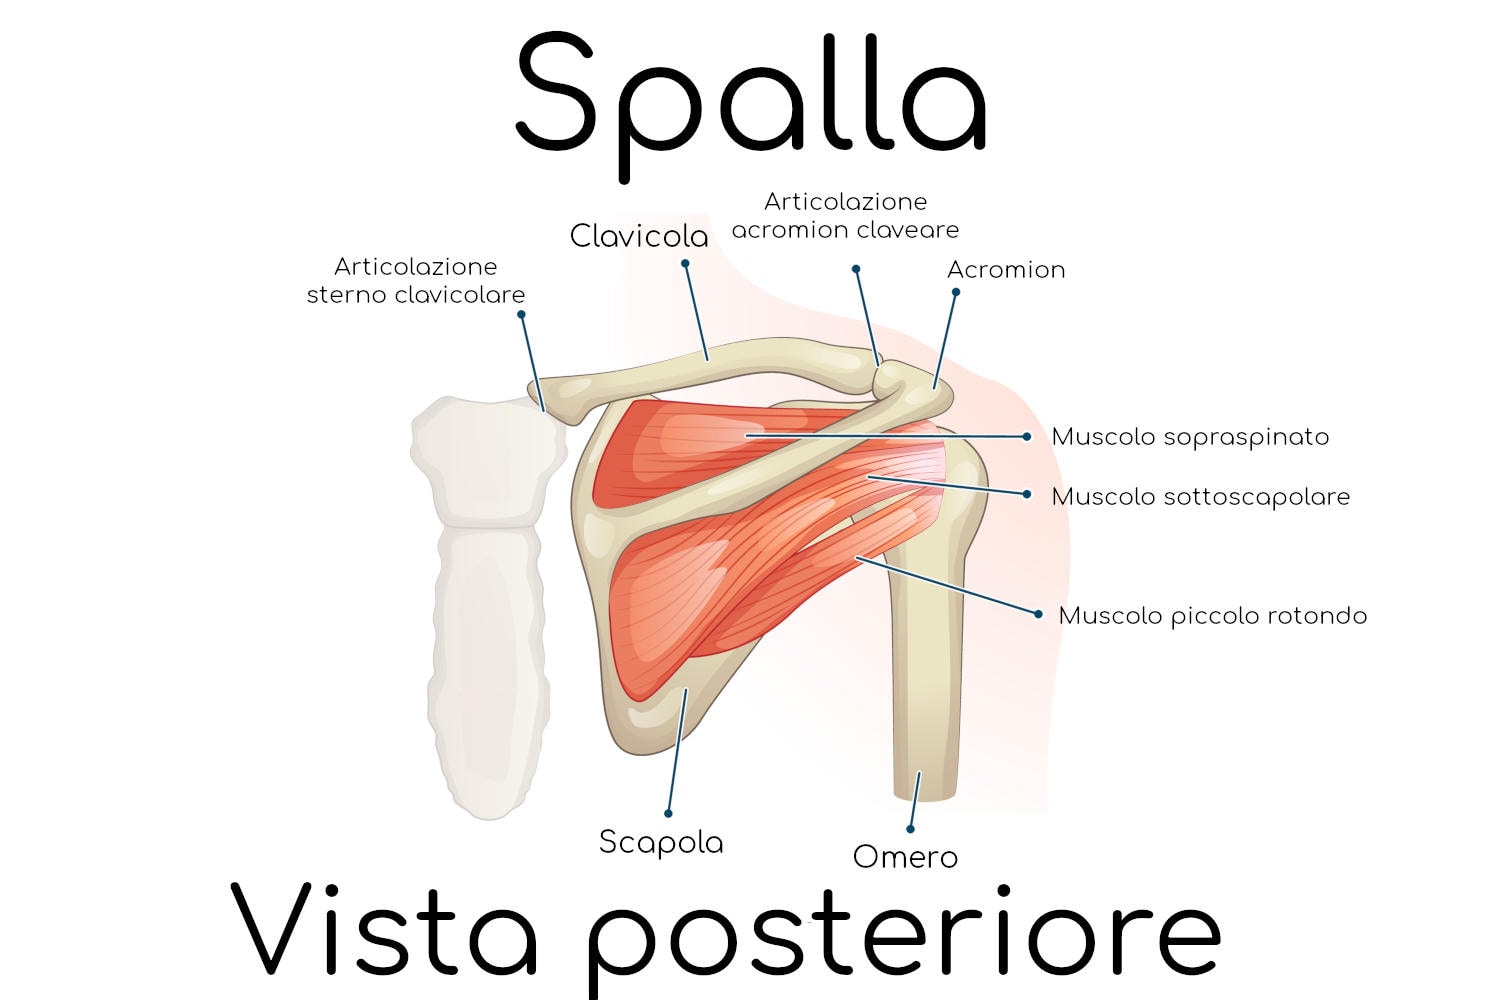

Anatomia della spalla

La spalla viene più propriamente chiamata in medicina “cingolo scapolare” ed è una articolazione “a sfera” (enartrosi). Permette di unire l’arto superiore, e nello specifico il braccio, al tronco con il quale si articola.

La spalla è costituita da 3 ossa:

- scapola

- clavicola

- omero (con la sua parte superiore, chiamata testa).

Queste ossa si articolano tra di loro mediante legamenti, tendini e altre strutture anatomiche, costituendo le seguenti articolazioni:

- Scapolo – omerale (anche detta gleno – omerale, dal nome della cavità glenoidea della scapola che si articola con la testa dell’omero)

- Sotto – deltoidea

- Scapolo – toracica

- Sterno – costo – clavicolare

- Acromion – clavicolare

Grazie alla sofisticata anatomia la spalla è in grado di muoversi nelle tre direzione dello spazio:

- Adduzione, ovvero l’avvicinamento dell’arto superiore al tronco

- Abduzione, ovvero l’allontanamento dell’arto dal tronco

- Rotazione dell’arto attorno al proprio asse